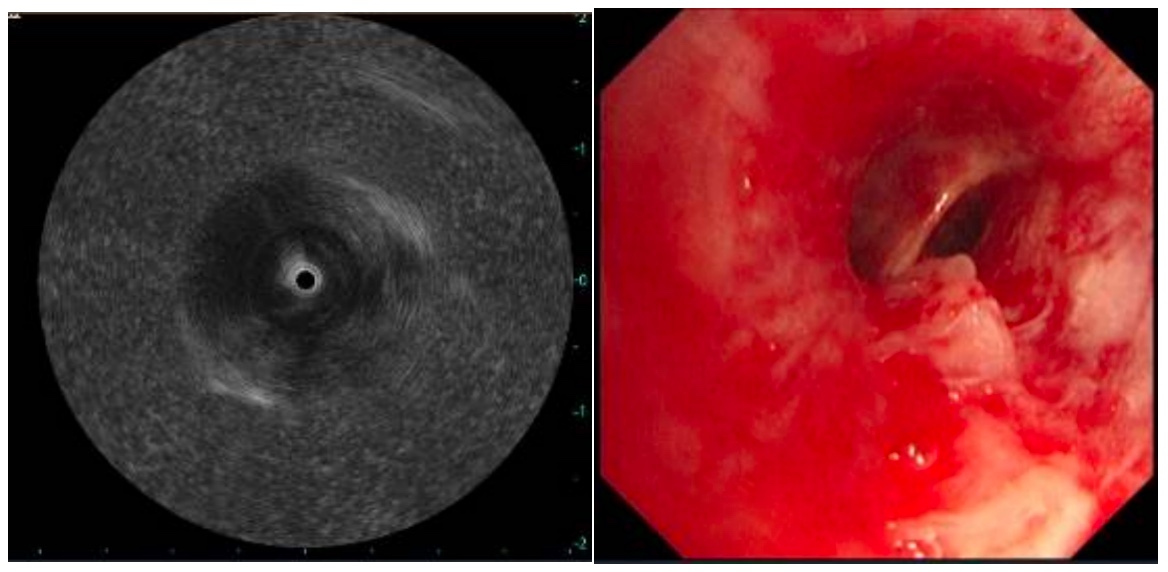

术中,医生将直径仅约2毫米的超声微探头经支气管镜送入气道,对目标区域进行360°实时扫描,清晰显示病灶及其周边血管关系,实现了“精准导航”。在超声实时监测下,团队成功钳取8块高质量组织标本。整个手术过程出血极少,患者术后仅轻微咳嗽,恢复良好。

术后第三天,病理结果出来了:浸润性肺腺癌。尽管这个诊断结果令人沉重,但明确的诊断让后续治疗有了清晰的方向。

超声小探头引导下经支气管镜肺活检术的成功开展,标志着医院呼吸介入诊疗能力实现新突破。该技术可深入至第六、七级支气管,触及肺外周、肺门深部病灶;通过实时超声成像提升活检准确率和安全性。相较于传统方法,这种微创技术仅通过气道自然腔道进行操作,体表无创口,出血风险低,患者痛苦小,术后恢复快,能有效缩短诊断周期,为后续治疗争取宝贵时间。